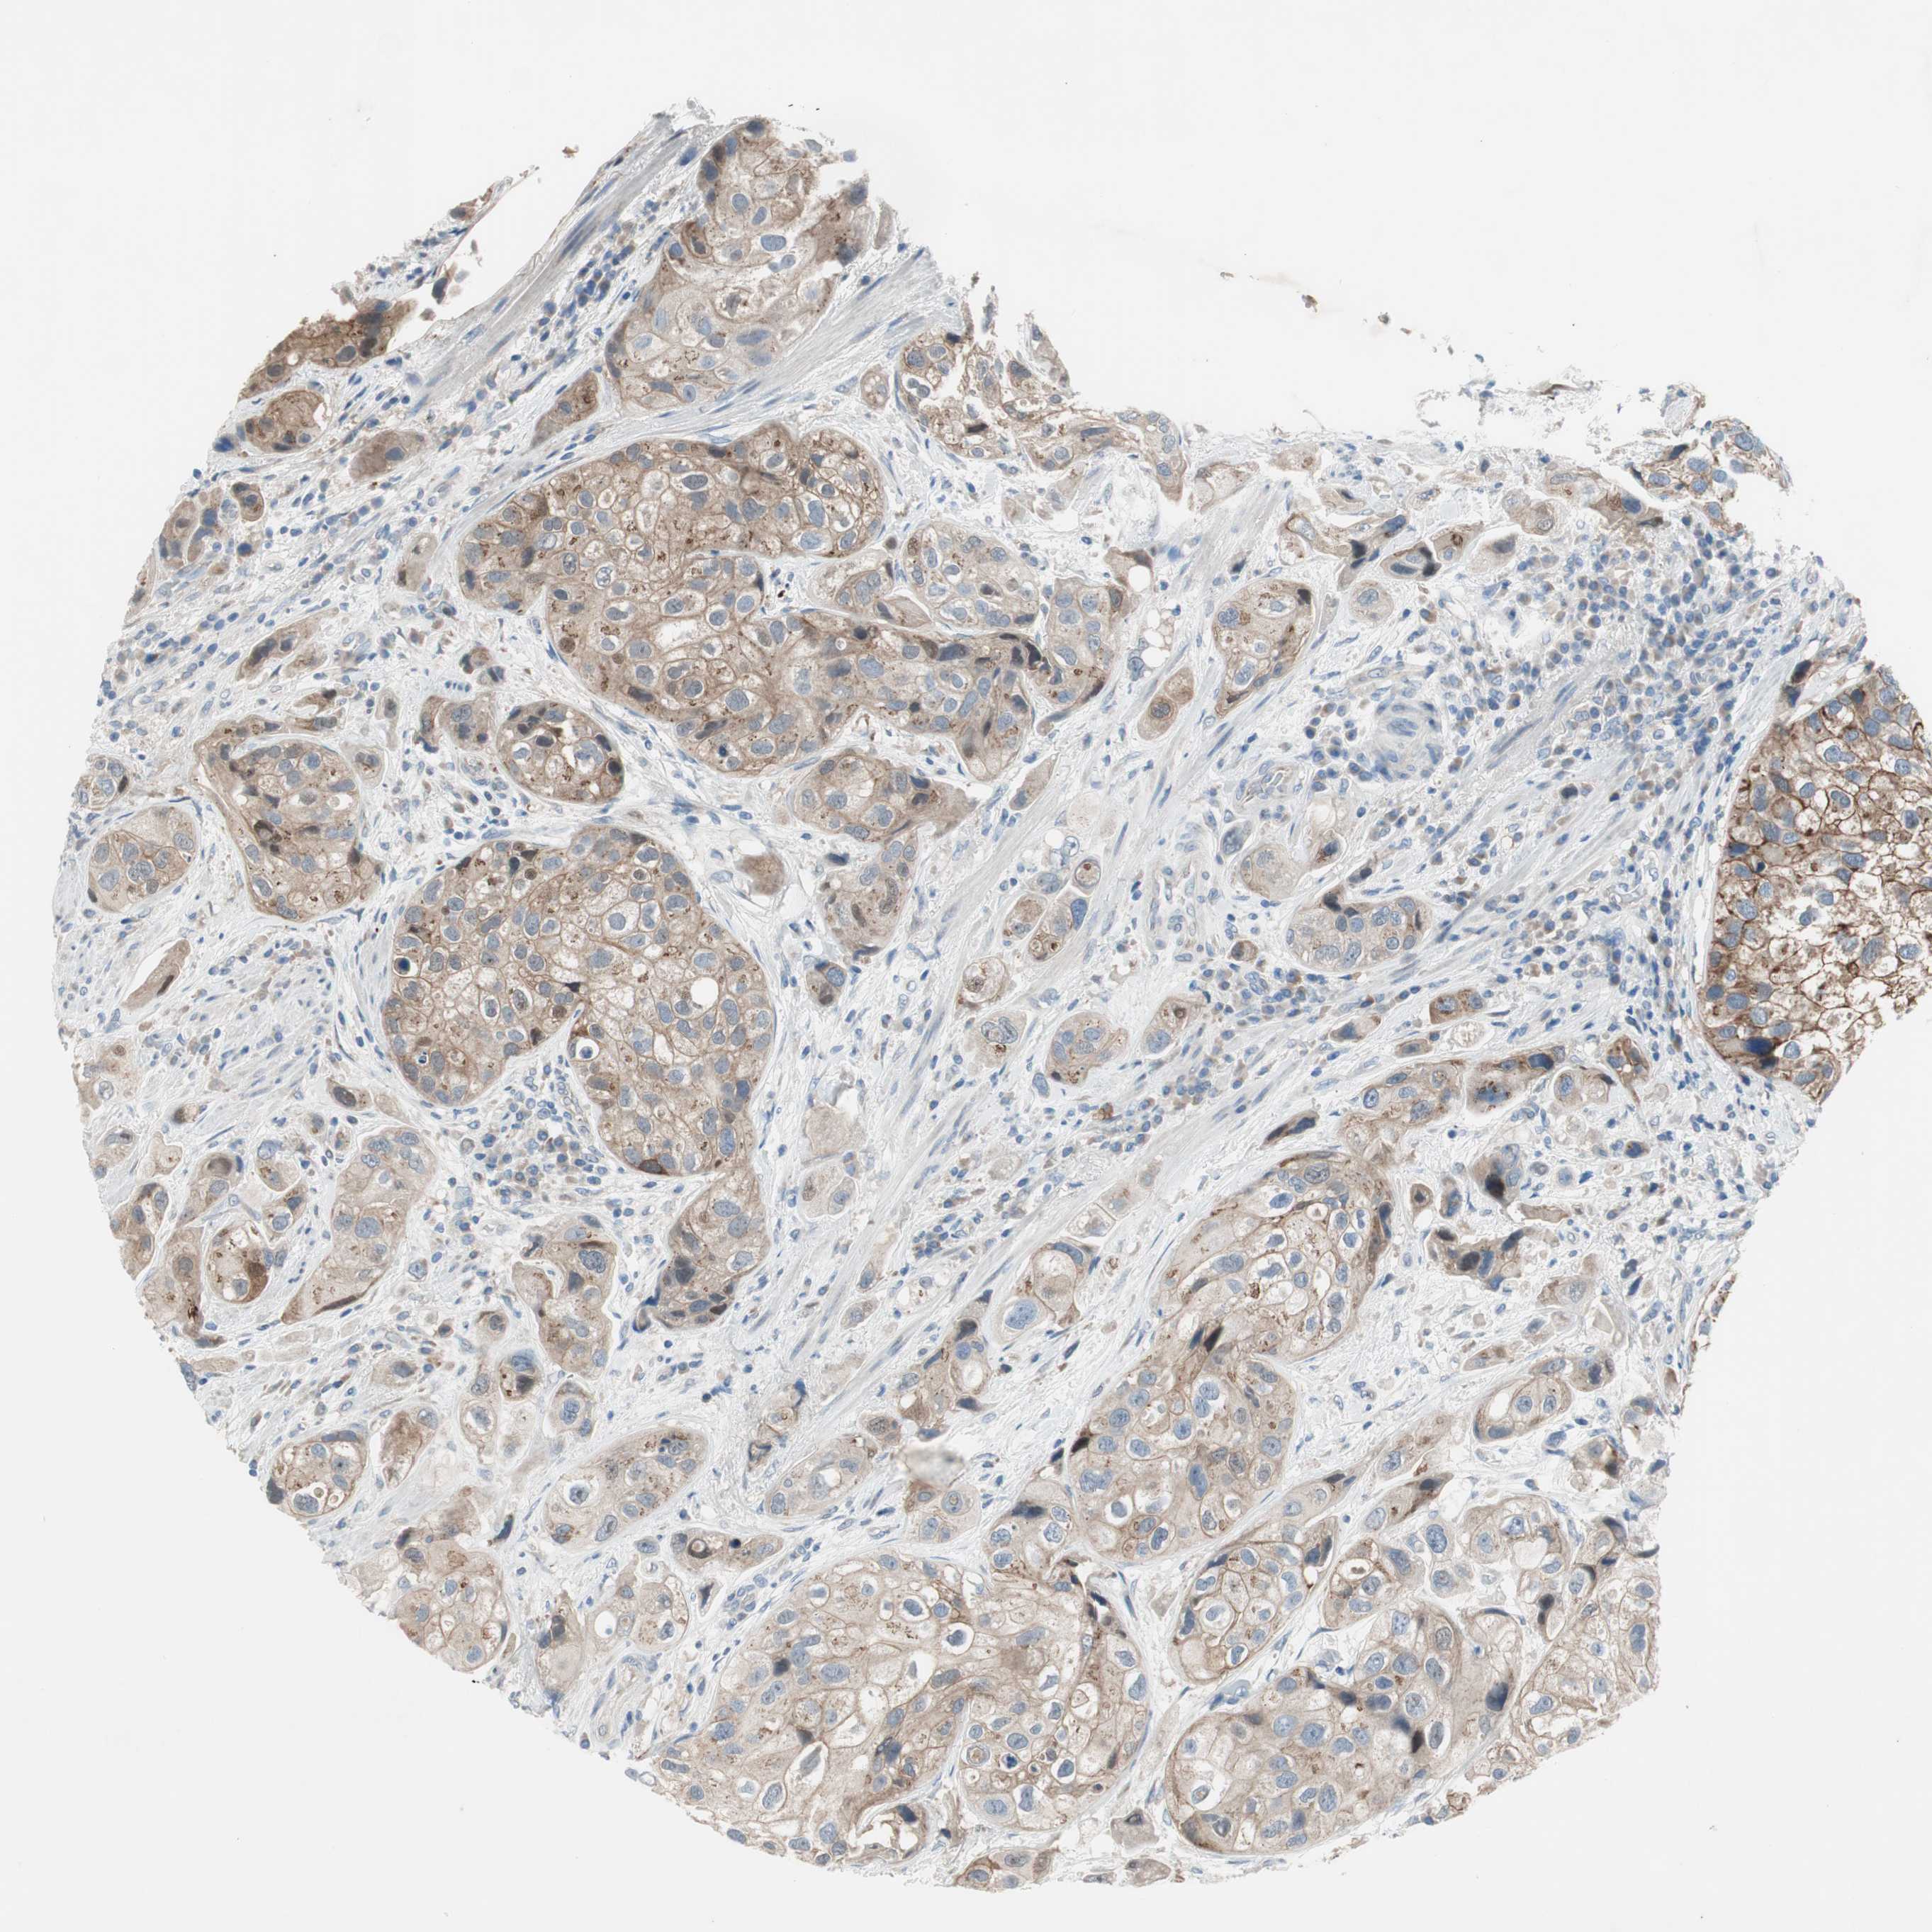

UROTHELIAL CANCER - Protein expressioni

A mouse-over function shows sample information and annotation data. Click on an image to view it in a full screen mode. Samples can be filtered based on level of antibody staining by selecting one or several of the following categories: high, medium, low and not detected. The assay and annotation is described here.

Note that samples used for immunohistochemistry by the Human Protein Atlas do not correspond to samples in the TCGA dataset.

Antibody stainingi

Antibody staining in the annotated cell types in the current human tissue is reported as not detected, low, medium, or high, based on conventional immunohistochemistry profiling in selected tissues. This score is based on the combination of the staining intensity and fraction of stained cells.

Each image is clickable and will lead to virtual microscopy that enables deeper exploration of all samples and also displays staining intensity scores, fraction scores and subcellular localization as well as patient and tissue information for each sample.

Antibody HPA009040

Antibody HPA024566

Staining

High

Medium

Low

Not detected

Intensity

Strong

Moderate

Weak

Negative

Quantity

>75%

75%-25%

<25%

None

Location

Nuclear

Cytoplasmic/membranous

Cytoplasmic/membranous,nuclear

Urothelial carcinoma, High grade